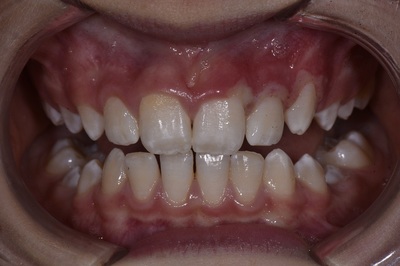

Признаки хронической формы:

Фото 2. Хроническая форма заболевания проявляется застойным переполнением кровью сосудов и отёчностью слизистой дёсен, кровоточивостью и деформацией десны.

- опухшее состояние десны;

- болевые ощущения во время приёма пищи;

- болезненность во время чистки зубов;

- переполнение крови в десне;

- отслаивание дёсенных сосочков от зубов.

Выявить хроническую форму гингивита сможет только врач.